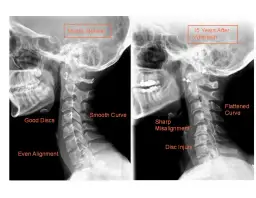

Skręcenie i zwichnięcie kostki to dwa różne rodzaje urazów, które często są mylone. Skręcenie kostki polega na naciągnięciu lub zerwaniu więzadeł, które stabilizują staw, natomiast zwichnięcie to przemieszczenie kości w stawie. Objawy skręcenia obejmują ból, obrzęk oraz ograniczenie ruchomości, podczas gdy w przypadku zwichnięcia może wystąpić widoczna deformacja stawu.

- Skręcenie: Ból, obrzęk, trudności w poruszaniu się, brak deformacji stawu.

- Zwichnięcie: Silny ból, obrzęk, widoczna deformacja, niemożność poruszania stawem.